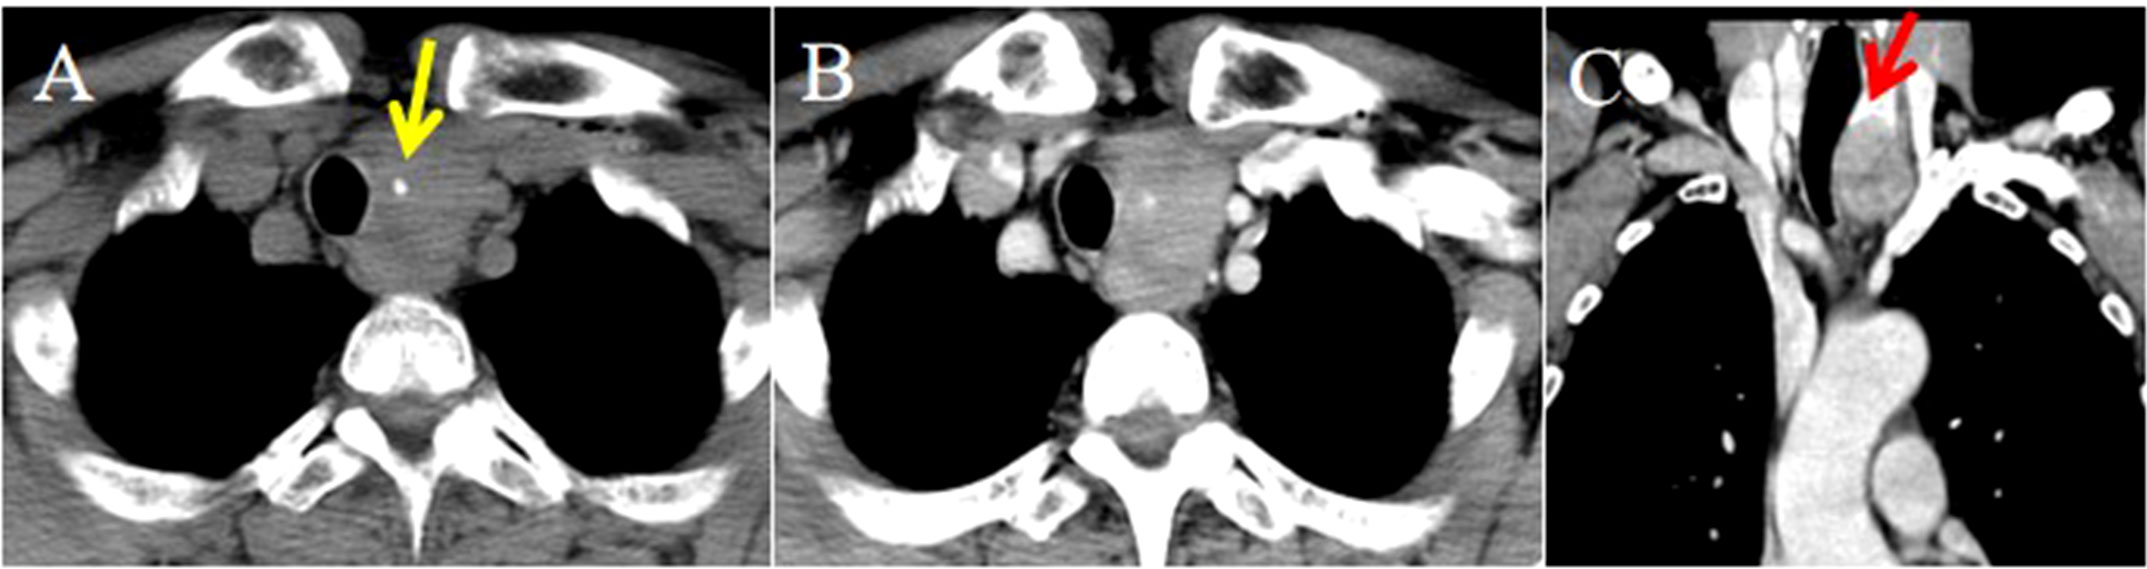

Objective: To summarize the clinical characteristics and imaging features of intrathyroid thymic carcinoma (ITTC), along with diagnostic and therapeutic approaches, to increase awareness of this rare disease. Methods: We retrospectively analyzed 14 patients with ITTC confirmed by core needle biopsy (CNB) and surgery combined with immunohistochemistry. The clinical and imaging findings, treatment, pathological findings and follow-up data of these patients were reviewed. Results: Thirteen patients were newly diagnosed and one relapsed at the original surgical site. All tumors were solitary, mostly located in the lower neck or upper chest, often in the tracheoesophageal groove with or without extension to the thyroid’s lower pole, and approximately two-thirds of patients presented with hoarseness. On CT, most lesions appeared as irregular, low-density soft-tissue masses, with calcification in two cases; contrast-enhanced CT revealed mild heterogeneous or homogeneous enhancement, and over half exhibited an arc-shaped interface with adjacent thyroid tissue. Most tumors were locally advanced, invading muscles, the supraclavicular fossa, tracheoesophageal groove, esophagus, tracheal wall, or mediastinal vessels. The diagnostic accuracy of fine-needle aspiration biopsy (FNAB) was low, whereas core needle biopsy (CNB) combined with immunohistochemistry was reliable. Ten patients underwent radical surgery, of whom three received adjuvant chemoradiotherapy and four adjuvant radiotherapy; four patients received radical chemoradiotherapy, and one received combined therapy including anlotinib, a novel tyrosine kinase inhibitor. The median follow-up was 86 months (range, 25–146), and three surgically treated patients developed local recurrence or pulmonary metastasis. Conclusion: CNB combined with immunohistochemistry is recommended when the characteristic and imaging manifestations suggest a diagnosis of ITTC. Especially for locally advanced cases, imaging-based diagnosis can be useful for analysis and to guide treatment.